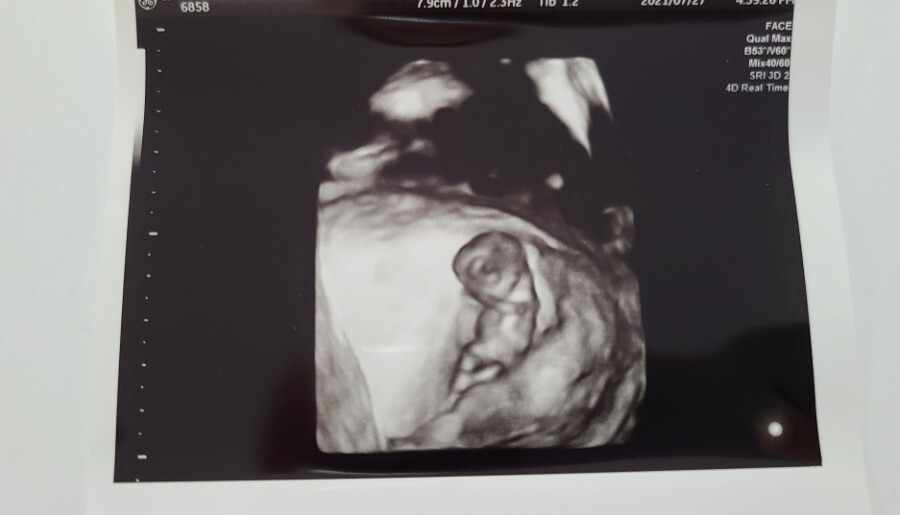

오늘은 10주 차에 산부인과에 다녀온 병원 방문기를 적어보려고 해요.

전 지난 7월 27일 한창 더웠을 시기에 병원에 다녀왔어요.

10주 차부터는 보통 질 초음파가 아닌 복부 초음파로 아기의 상태를 확인할 수 있다고 하셔서 복부 초음파로 아기의 상태를 확인했어요.

복부 초음파로 확인한 우리 아기의 크기는 3.45cm로 주수에 맞게 잘 크고 있다고 하시더라고요.

심장 소리도 지난번보다 더 우렁차졌다고 하셔서 조금은 안심할 수 있었고 이젠 제법 사람의 형태가 보이는 것 같아 신기하기도 했어요.